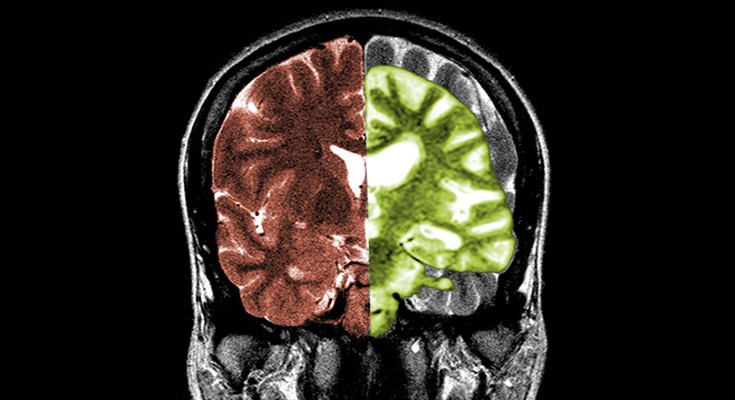

RNA-sequencing analysis of cells in the human cortex enabled identification of diverse cell types, revealing well-conserved architecture and homologous cell types as well as extensive differences when compared with datasets covering the analogous region of the mouse brain.

Whether cell types in the brain have been conserved during evolution is not clear. A comparison of the molecular recipes that define brain cell types in humans and mice reveals similarities and differences between species.

• Matthew G. Keefe

•  & Tomasz J. Nowakowski

The brain

The human brain isn’t much to look at. In the hand, it is a jelly-like mass, easily deformed by touch. But its unassuming appearance belies complex inner workings, many of which are still a mystery to scientists.